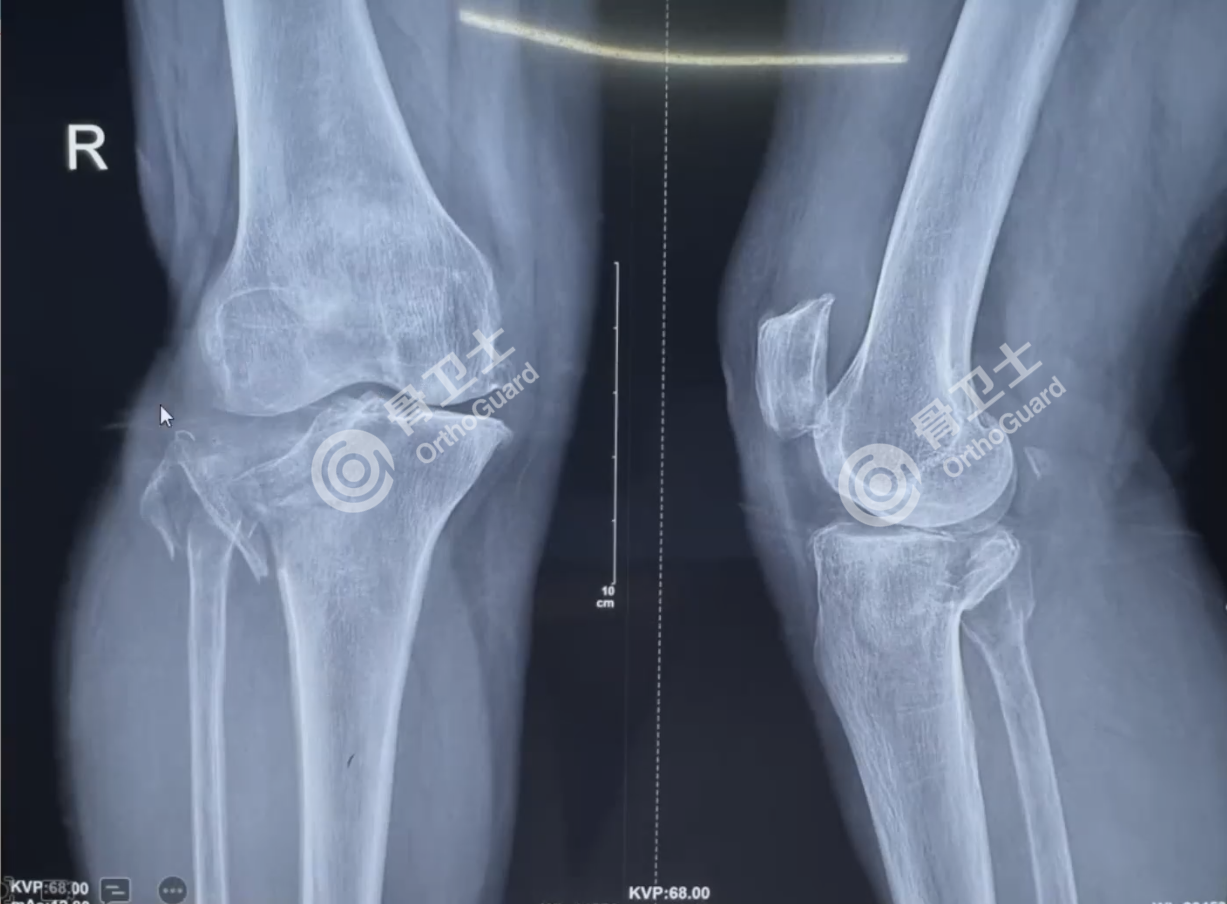

基本情况:男,67岁,因左膝关节疼痛3年余入院.。

查体:左膝关节内翻畸形,皮温正常,左膝髌下脂肪垫及膝关节内侧压痛明显,屈曲100°,伸直30°,髌骨研磨试验双侧(+),浮髌试验双侧(-),膝腱反射双侧(++),跟腱反射双侧(++),双下肢肌力正常、浅感觉正常。

诊断:左膝关节骨性关节炎,膝关节内翻严重。

治疗方案:拟行左人工全膝置换术。

▲患者影像资料

对于该患者的治疗,周乙雄教授认为,此患者有施行人工膝关节置换的适应症,关节间隙变窄、消失,局部硬化、疼痛、活动受限,屈膝30°畸形,合并内翻畸形。手术应以股骨和胫骨的正常轴线为准,放到正常的外翻角度,在此原则上,边截骨边松解软组织,这两者是相辅相成的。手术过程中,随时测量力线是否正确,若有不妥,随时矫正。